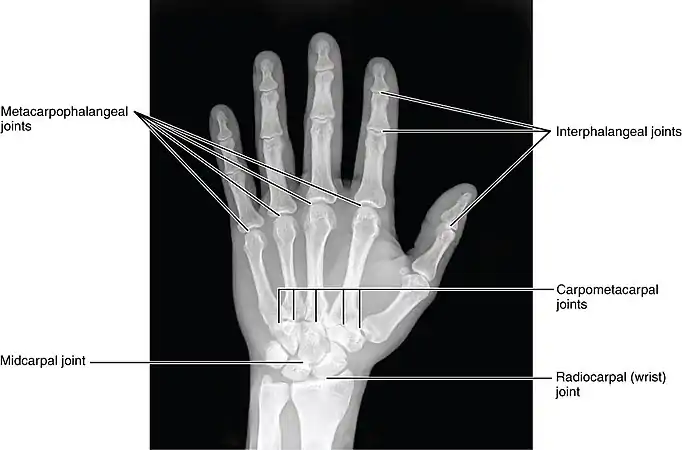

Hand bones. Note the thumb has no blue middle phalanx. Hand Joints, X-ray

Hand Joints, X-ray

Location

Finger fractures are identified by the bone on which they occur. Fingers are numbered 1 to 5, with 1 being the thumb. The distal (tip) finger bones are divided into tuft (the very tip of the bone, at the end of each finger), shaft (the thinner middle section), and base. The rest of the finger bones (the middle finger bones, and the proximal or innermost finger bones) are divided into base, shaft, and condyle (outer end). Extensive tendons surround the joints and move the fingers. On the front and back of each finger is a digital nerve and artery; these can also be injured when the finger is broken.[1]

The AO Foundation/Orthopaedic Trauma Association (AO/OTA) classification generates language-neutral numeric codes for describing broken fingers. They run 78[meaning a fracture of the phalanges of the hand].[number-code of the finger, with thumb=1 and the little finger=5].[number-code of phalanx, counting 1 to 3 outwards from the hand].[number-code of location on the bone, with 1 being the inner end, 3 the outer, and 2 in-between]. So, for instance, 78.1.1.1 means a fracture to the thumb's innermost bone, at the inner end (the base of the thumb). A letter can be added to describe the fracture pattern.[4]